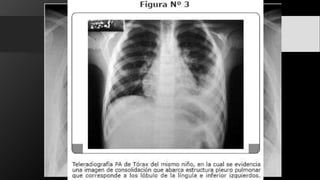

• La radiografía PA de tórax revela un área de condensación unilateral con la presencia de

broncograma aéreo localizada en cualquier lóbulo; sin embargo, predomina en lóbulos

medio e inferior.

• Su apariencia es similar a la de cualquier proceso neumónico